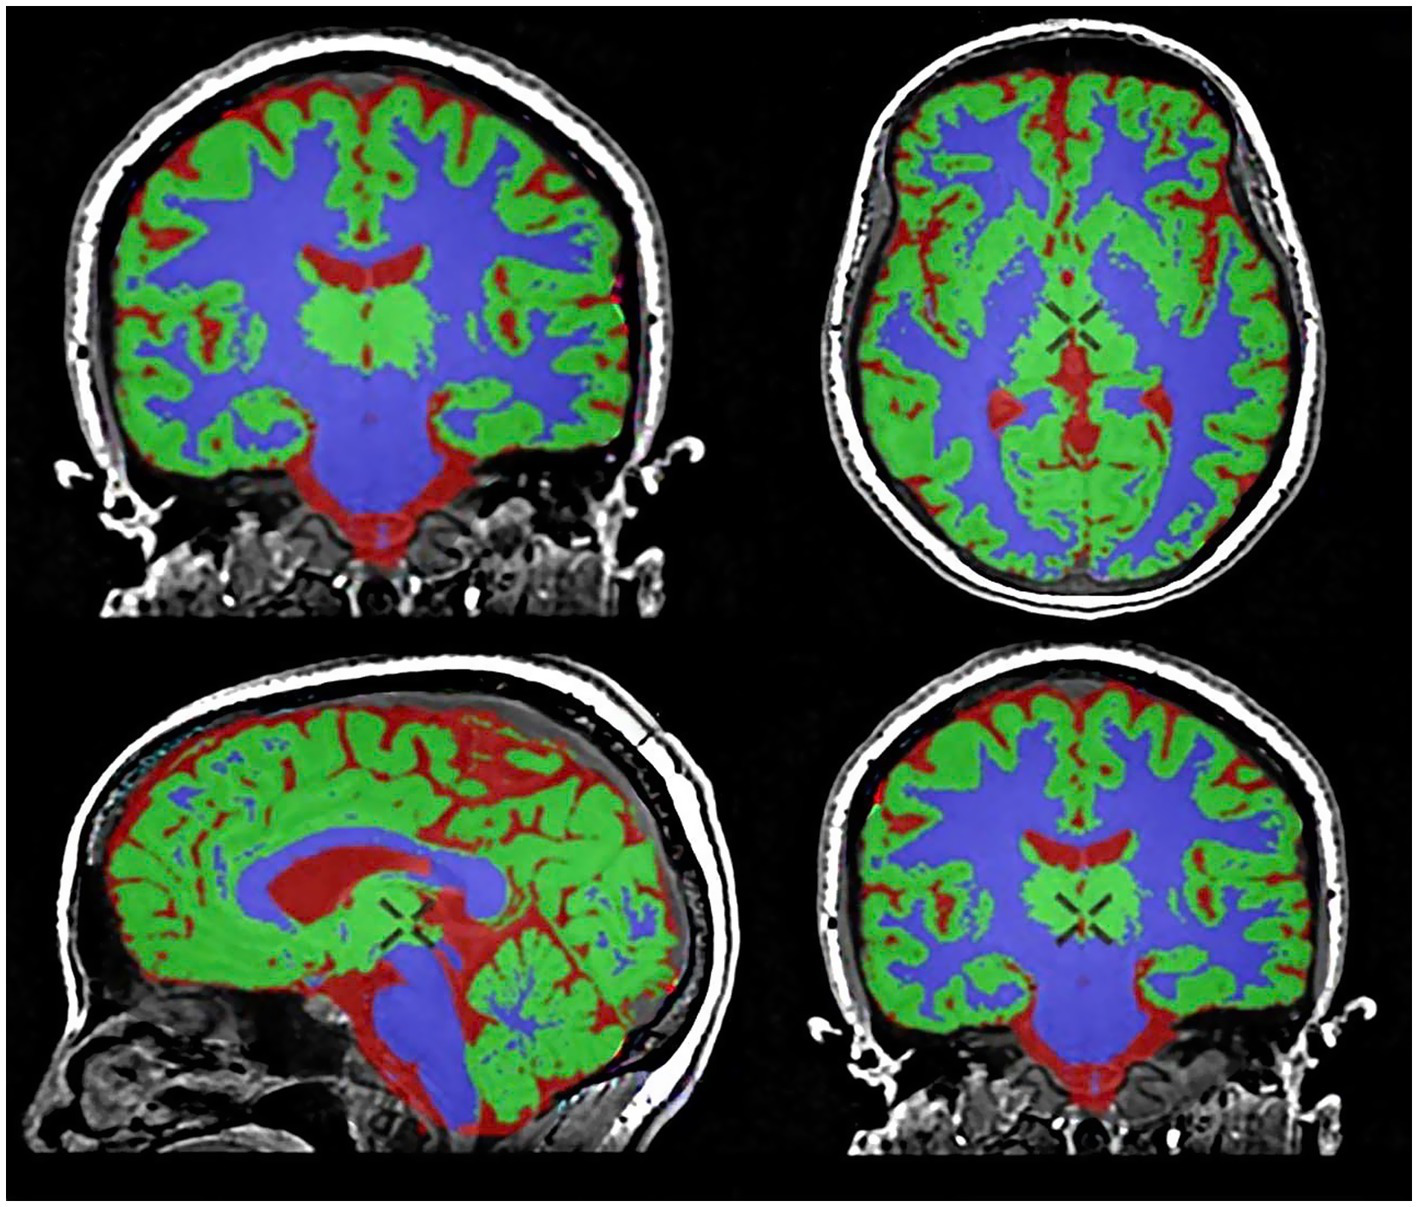

The original 3D T1-weighted BRAVO images were seamlessly processed using the Quantib™ Brain tool integrated within the advanced GE Healthcare workstation. This tool provided an automated workflow for brain segmentation, volumetric quantification, visualization, and reporting (Figure 1) (29).

Figure 1

Brain segmentation and volumetric analysis using the Quantib™ Brain tool. Gray matter (GM) is segmented in green, white matter (WM) in violet, and cerebrospinal fluid in red.

For each participant, the following brain volume indices were automatically measured and analyzed: (1) total gray matter volume (GMV), (2) total white matter volume (WMV), (3) total cerebrospinal fluid volume (CSF), and (4) total intracranial volume (TIV) = GMV + WMV + CSF. Furthermore, to account for interindividual differences in head size, normalized brain volumes were calculated: (5) normalized gray matter volume (nMV) = GMV / TIV, and (6) normalized white matter volume (nWM) = WMV / TIV. This standardized approach ensured robust and reproducible brain volume measurements, facilitating interparticipant comparisons while accounting for anatomical variability.